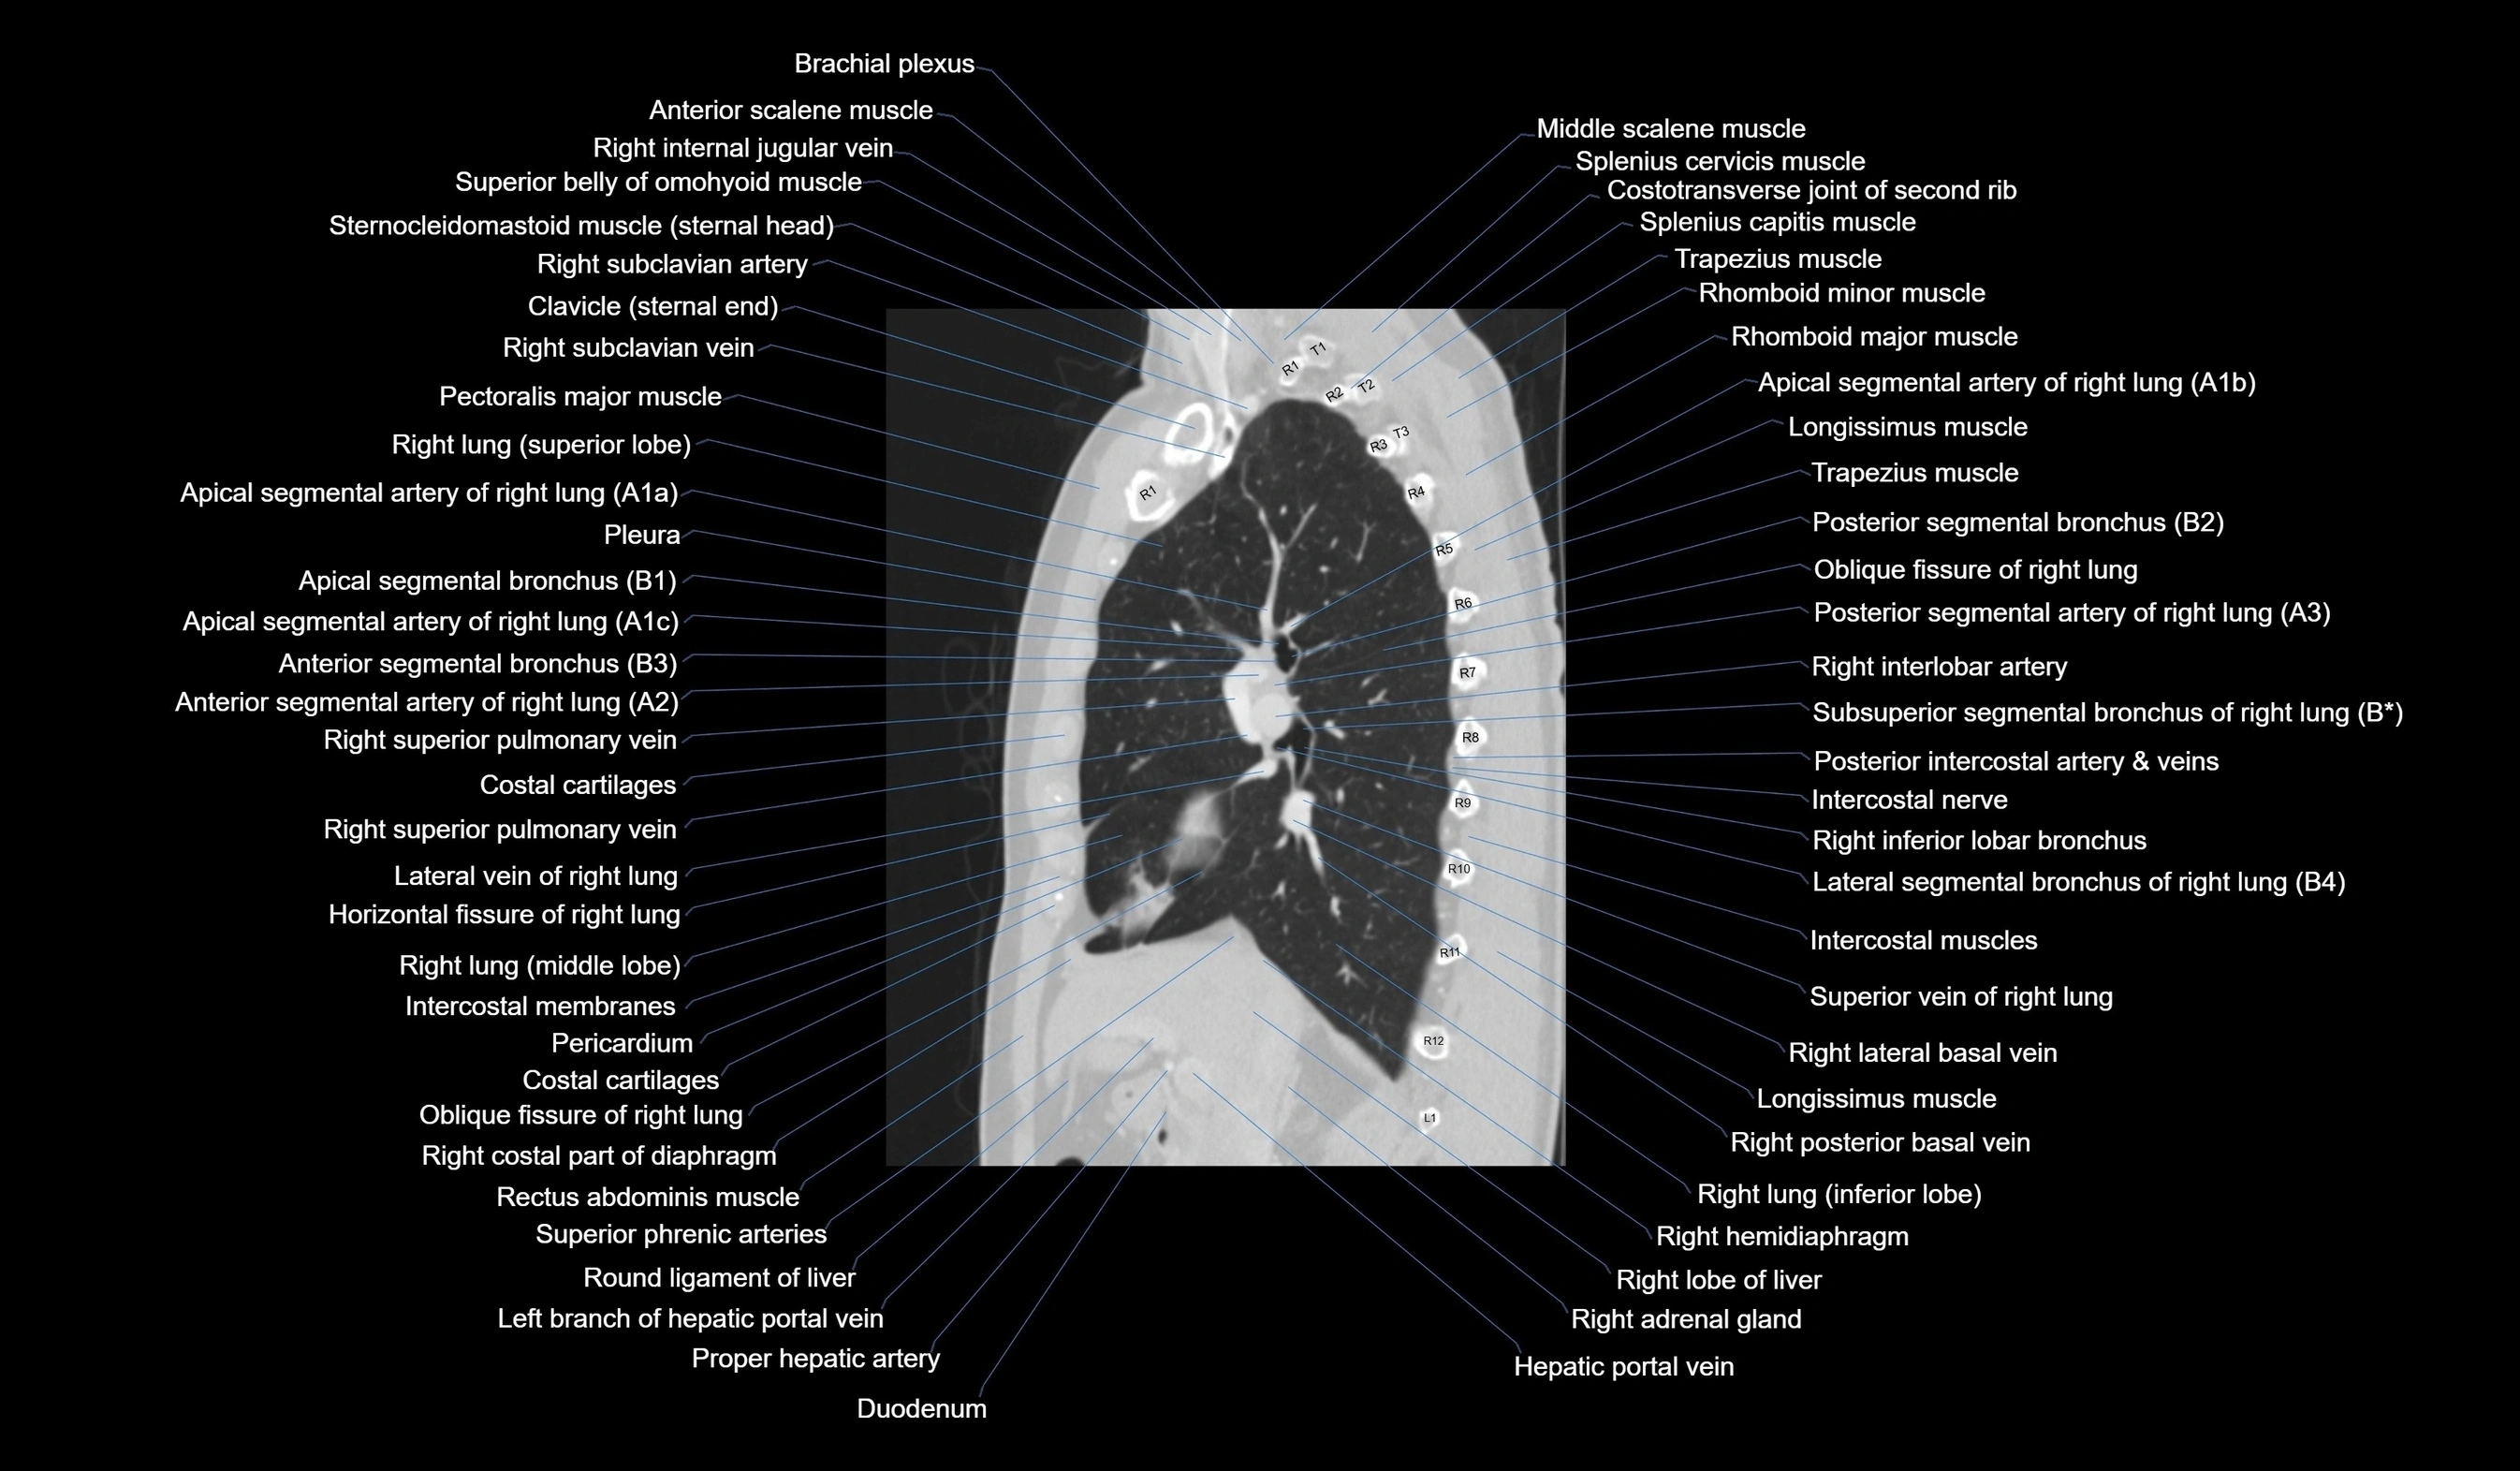

CT images